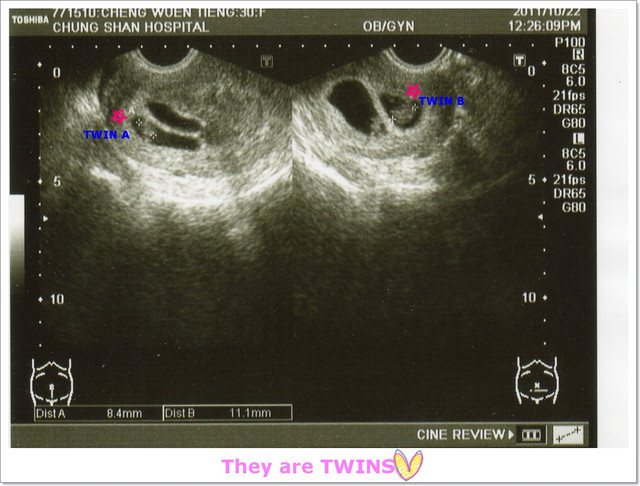

今天同樣也是照陰超,不過大概是羅醫生的經驗很豐富,所以不太有不舒服的感覺。

羅醫生還說,不用擔心子宮後傾不容易受孕,妳都懷雙胞胎了>//////

接著~要聽寶寶的心跳,羅醫生請我憋氣5秒,超音波室出現咚咚~咚咚~咚咚的心跳聲,

隔了一個禮拜,寶寶們都有乖乖的在媽咪的肚子裡長大喲:)